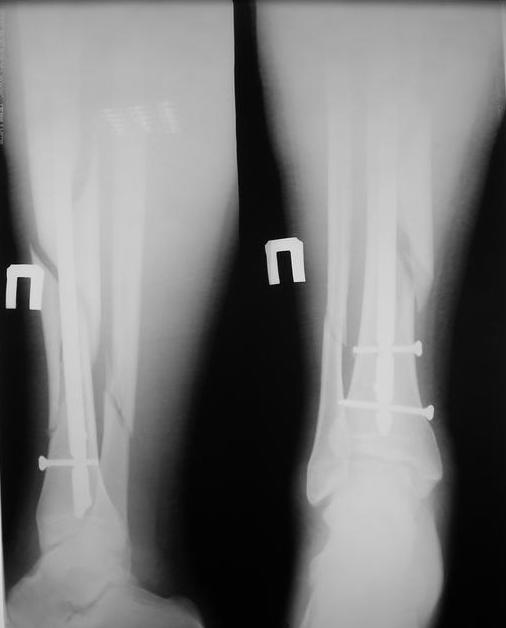

У нас был молодой пациент М.(26лет), травма 25 января 2009г, катался на лыжах и получил травму. Поступил к нам в отделение в экстренном порядке. При обследованиии выявлен закрытый винтоообразный оскольчатый перелом правой большеберцовой кости и косой перелом малоберцовой кости на границе средней и нижней трети. Выполнен интрамедуллярный блокируемый синтез большеберцовой кости, оси и длина конечности восстановлена. После операции пациент ходил с полной нагрузкой. Через 3 месяца на контрольных рентгенограммах сращения нет, динамизации не выполняли, так как оскольчатый перелом.(снимки в динамике прилагаются). Посоветуйте, что в данном случае делать наиболее целесообразно?

Остеосинтез, похоже, сделали с перерастяжением, так что динамизировать, наоборот, надо было еще и раньше обычного, недели через 4 после операции.

Да есть диастаз, но скорее от смещения осколка по ширине, а не по длине - по малоберцовой длина нормальна.

И малоберцовая перерастянута. По большеберцовой видно щель по переднему контуру, промежуточный фрагмент к этой области не имеет отношения.

Отсутствие уверенных признаков сращения неделям к 8 - надо динамизировать. Тут уже 3,5 мес., есть щель из-за смещения по длине. Дальнейшее консервирование ситуации тут не решает никаких проблем, а вот создать их может. Динамизация с нагрузкой и диастаз уменьшит, и репаративный процесс "освежит".